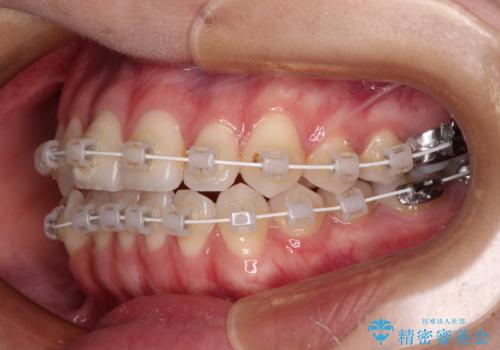

- 矯正装置

- 審美装置

右側の奥歯は、上が外側に転位した鋏状咬合を呈しており、前歯のデコボコ改善と並行して咬み合わせを改善していく必要がありました。

装置はワイヤー装置でもインビザラインのマウスピースでもどちらでも適用でしたが、自己管理の煩わしさを嫌い、ワイヤー矯正にて治療を行うこととしました。

ワイヤー矯正を選択されたため、鋏状咬合を確実に改善するために補助装置を併用することとしました。

ワイヤー装置でもマウスピースでも、どちらでも適用の症例でしたが、片側の鋏状咬合はマウスピース矯正ではしっかりと改善できる可能性が低いことや、何と言っても自己管理の煩わしさがないことから、ワイヤー装置を選択されました。